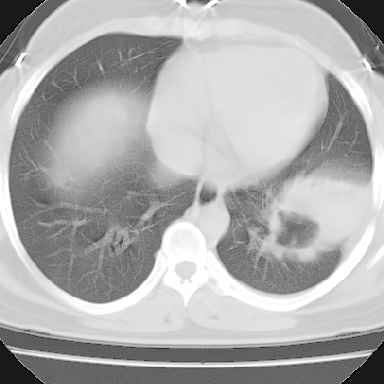

偏心性厚壁空洞,壁结节,胸膜肥厚粘连,双肺多发性小结节灶。这么多典型征象,即使错了也错的有道理!

病灶与临床特点:1 位于下肺外围.2 与胸膜关系密切并明显胸膜反应.3 空洞内壁虽见壁结节,但还是较光滑.4 病灶周围明显渗出.5 另肺内多发小结节.6 临床症状轻,发病时间短.综合考虑:肺内特殊感染(霉菌感染).

支持。另外,双侧腋下似见增大淋巴结影,有侧乳腺4、5点处皮下高密度结节影是什么?食管中下段有没有问题?病人比较年轻,因此诊断恶性肿瘤要慎重,多结合临床和其他检查,多考虑一些,也可短期抗炎治疗后复查。